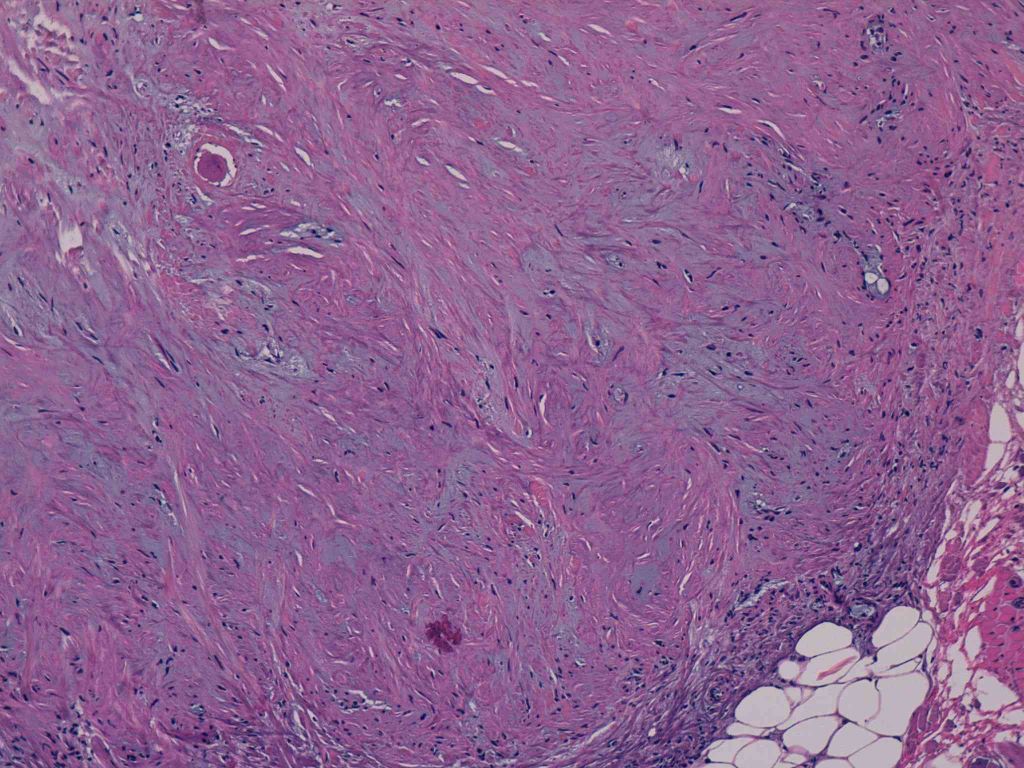

22 -- image_2011y09m11d_15h10m46s.jpg